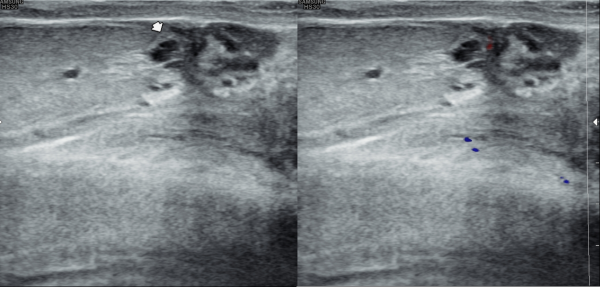

5년전 내원 당일 정낭의 초음파 검사상 좌측 정낭 낭종이 의심되는 사진입니다.

An ultrasound image of the seminal vesicles taken on the day of the visit five years ago, showing a suspected cyst in the left seminal vesicle.

5년후 내원 당일 정낭의 경직장 전립선 초음파 검사상 정낭의 낭종들이 커지고 있는 사진입니다.

A transrectal prostate ultrasound image of the seminal vesicles taken on the day of the visit five years later, showing enlargement of seminal vesicle cysts.